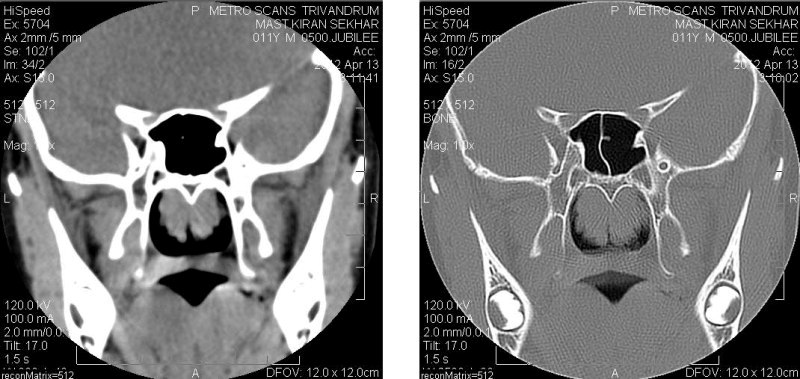

An X-ray Lateral Neck or a CT image of the Nasopharynx will show enlarged adenoid. A flexible nasal Endoscopy also helps to make the diagnosis. A sleep study if it can be done is of great use.